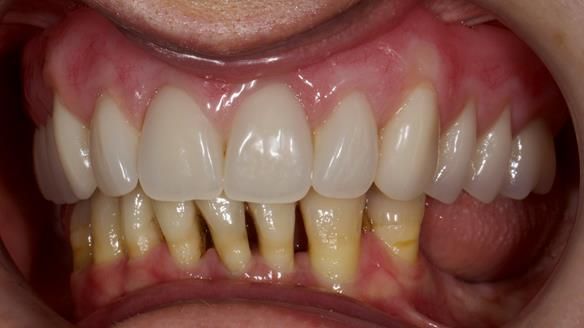

She had previously suffered from generalised periodontitis – stage IV, grade C, currently stable, with reduced attachment across the upper arch.

By the time she came to me, her periodontal condition was stable — but the aesthetics in the upper jaw were very poor.

We provided her with an immediate upper denture (Mk 1), followed by a definitive metal-based upper denture (Mk 2). A lower removable partial denture was discussed, to be made only if needed once the upper treatment was complete. However, at review, this wasn’t necessary — Adnana had excellent neuromuscular control and function, even with a shortened dental arch (SDA).

- A restored smile, restored lip support, and a patient who owned the journey